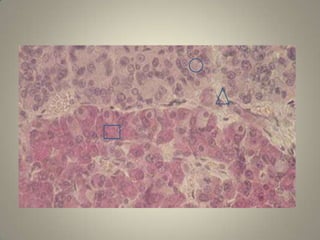

Histology of AdenohypophysisDepending upon the staining property-2 typesChromophobe cellsChromophil cells

Continued…Chromophobe cellsDo not possess granules Stained poorly Cells are not secretory in natureBelieved to be the precursors of chromophil cellsComprises about 50% of total cells

Continued…Chromophil cellsContain large number of granulesDarkly stained2 types based on staining natureAcidophilic or Alpha cells - 35%Basophilic or Beta cells     - 15%

Histology of AdenohypophysisDependingupon the staining property-2 typesChromophobe cellsChromophil cells

• 23.

Continued…Chromophobe cellsDo notpossess granules Stained poorly Cells are not secretory in natureBelieved to be the precursors of chromophil cellsComprises about 50% of total cells

• 24.

Continued…Chromophil cellsContain largenumber of granulesDarkly stained2 types based on staining natureAcidophilic or Alpha cells - 35%Basophilic or Beta cells - 15%